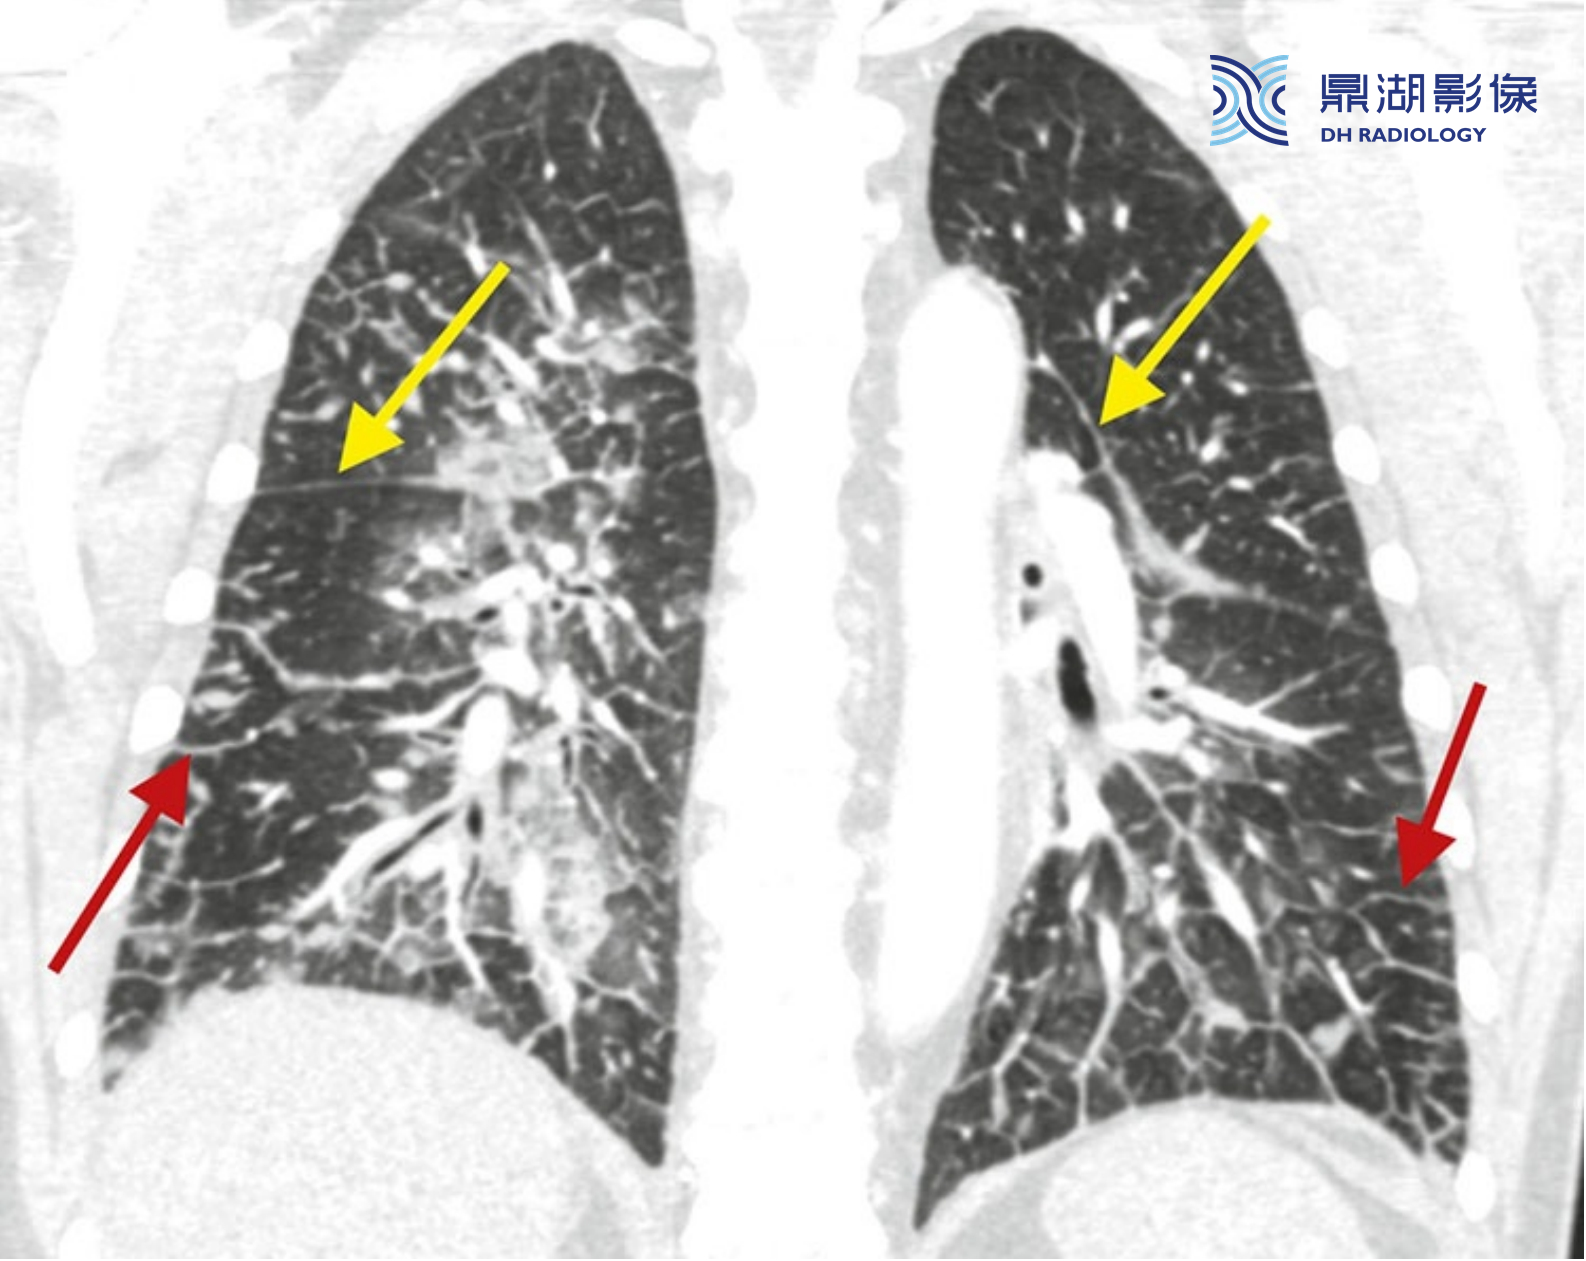

肺水肿伴小叶间隔和肺裂增厚。CT冠状位重组图像显示增厚的肺裂(黄箭),代表液体聚集在胸膜下间质,也可见小叶间隔平滑增厚(红箭)。